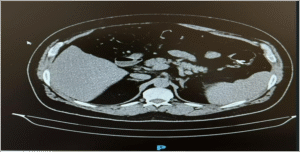

· CT Angiography:

- Dilated colonic veins in the right colon

- No evidence of splenomegaly, portal vein thrombosis, or liver cirrhosis